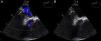

Se trata de un varón de 27 años, portador de prótesis mecánica tricúspide por válvula displásica desde hacía 4 años, sin otros antecedentes. Acude a urgencias por cuadro sincopal, refiriendo astenia y disnea durante 3 semanas. Los últimos controles del cociente internacional normalizado (INR) se encontraban por debajo de rango de anticoagulación (1,2 y 1,4). A la exploración presenta buen estado general, encontrándose afebril, eupneico, manteniendo una saturación de O2 por pulsioximetría del 94%, normotenso (TA 110/72mmHg) y auscultación cardiaca rítmica con soplo en foco tricuspídeo. Se realiza una analítica donde destaca un INR de 1,5 y un electrocardiograma con taquicardia sinusal a 100lpm con signos de crecimiento de cavidades derechas. En la ecocardiografía transtorácica (ETT) se aprecian signos de trombosis protésica con un oclusor fijo en posición cerrada y el otro fijo en semiapertura, con gradiente auriculoventricular tricuspídeo medio de 13mmHg (previo de 5mmHg) y una disfunción biventricular moderada (FEVI 35-40%). Ingresa en UCI en situación clínica estable para realización de fibrinólisis sistémica con activador de plasminógeno tisular recombinante a dosis de 100mg infundidos en 2h, seguido de anticoagulación con heparina sódica y antiagregación con AAS. A las 24h sufre un empeoramiento súbito con hipoxemia grave (PaO2/FiO2 50mmHg) e hipotensión arterial (TAS 80mmHg), obligando a conexión a ventilación mecánica y administración de fármacos vasoactivos. Ante la clínica y la fibrinólisis reciente se sospecha de tromboembolismo pulmonar agudo (TEP) y se administra nueva fibrinólisis con 40mg de tenecteplase en bolo por su rapidez de actuación y la gravedad del enfermo, produciéndose leve mejoría del intercambio gaseoso (PaO2/FiO2 122mmHg). Se realiza nueva ETT urgente que muestra persistencia de la disfunción protésica con gradientes elevados (gradiente medio de 14mmHg) sin otros hallazgos. Durante los 3 días posteriores se mantiene más estable, en ventilación mecánica con persistencia de la hipoxemia moderada (PaO2/FiO2=150mmHg) y con apoyo de noradrenalina y dobutamina a dosis bajas, decidiéndose aplazar la cirugía de sustitución valvular hasta conseguir mayor estabilidad. En las siguientes 72h y a pesar del incremento de las medidas de tratamiento con ventilación protectora, maniobras de reclutamiento y colocación en posición de prono, evoluciona de forma desfavorable a hipoxemia severa refractaria (PaO2/FiO2 60mmHg). En las radiografías de tórax no se observan hallazgos patológicos por lo que se realiza una tomografía computarizada (TC) en la que se identifica un infiltrado alveolar en lóbulo inferior derecho sugerente de neumonía e importante cardiomegalia a expensas de una aurícula derecha (AD) dilatada (fig. 1A), sin signos de TEP. Dado que los hallazgos no justificaban el grado de hipoxemia se realiza una ecocardiografía transesofágica (ETE) en la que se vio una AD aneurismática muy dilatada (fig. 1B) con un foramen oval permeable (FOP) que condicionaba un shunt derecha-izquierda (fig. 2), persistiendo la TVP. Se procede a cirugía emergente con PaO2/FiO2 de 40mmHg que obliga a realizar inicialmente un bypass bifemoral parcial para oxigenación y, posteriormente, completo doble cava. Se realiza cierre del FOP y sustitución de la prótesis trombosada por otra modelo St. Jude. El postoperatorio trascurrió de manera satisfactoria, si bien desarrolló encefalopatía moderada que retrasó la extubación hasta el 5.° día del postoperatorio, y una disfunción renal aguda oligúrica. Fue dado de alta de UCI tras 21 días de ingreso asintomático y sin secuelas.

La TVP es poco frecuente, pero su morbimortalidad es elevada, requiriendo tratamiento de urgencia. La clínica depende de la rapidez de instauración de la obstrucción valvular, pudiendo ser brusca con insuficiencia cardiaca y edema pulmonar, hipoperfusión o shock, o más insidiosa con signos de disfunción derecha acompañada de soplo diastólico y/o ausencia de clics protésicos3. El diagnóstico se realiza mediante ecocardiografía con imágenes de trombos, aumento del gradiente transvalvular y disminución en la amplitud de los movimientos de los discos y del área valvular. Aunque la ETT es rápida y efectiva, el método de elección para su diagnóstico sigue siendo la ETE4, y no hay datos acerca de la utilidad del ecocardiograma tridimensional. La fibrinólisis constituye el tratamiento de elección para la TVP tricuspídea, reservando la cirugía como tratamiento de rescate5. Las complicaciones tras la fibrinólisis son escasas, siendo infrecuente la embolización sistémica y las embolias pulmonares clínicas. No hay una recomendación específica sobre cuál es el fibrinolítico de elección, aunque el activador del plasminógeno tisular recombinante es el más empleado6. Su pronóstico es malo, con una mortalidad elevada incluso en aquellos pacientes tratados con fibrinólisis (12%)7. La prevalencia de FOP es de hasta el 27% en series de autopsias8, por ello la importancia de descartarlo precozmente en los casos que se sospeche shunt intracardiaco mediante realización de ETE. Aunque la mayoría de los casos constituye una entidad benigna, existen situaciones en las que el aumento de presión en las cavidades derechas condiciona la aparición de un shunt derecha-izquierda9, como el fallo ventricular derecho o la compresión mecánica de la aurícula derecha. Clínicamente se han descrito varios grados de afectación según la magnitud del shunt, desde hipoxemia leve hasta, como nuestro caso, hipoxemia grave que obliga a una corrección quirúrgica inmediata. En el caso que nos ocupa, la TVP produjo un aumento de presiones derechas que ocasionó el shunt derecha-izquierda con hipoxemia grave, siendo esta una complicación muy infrecuente tras revisar la literatura existente (hemos encontrado casos similares tras endocarditis sobre válvula tricúspide9 y un solo caso por obstrucción protésica10). Desconocemos si el FO estaba presente previamente o bien se repermeabilizó por el aumento de presiones, ya que no se realizó una ETE al ingreso. Concluimos haciendo hincapié en lo infrecuente de esta complicación, pero en la necesidad de tenerla presente ante una semiología similar a la de nuestro caso por la necesidad de llegar al diagnóstico y realizar el tratamiento quirúrgico adecuado.